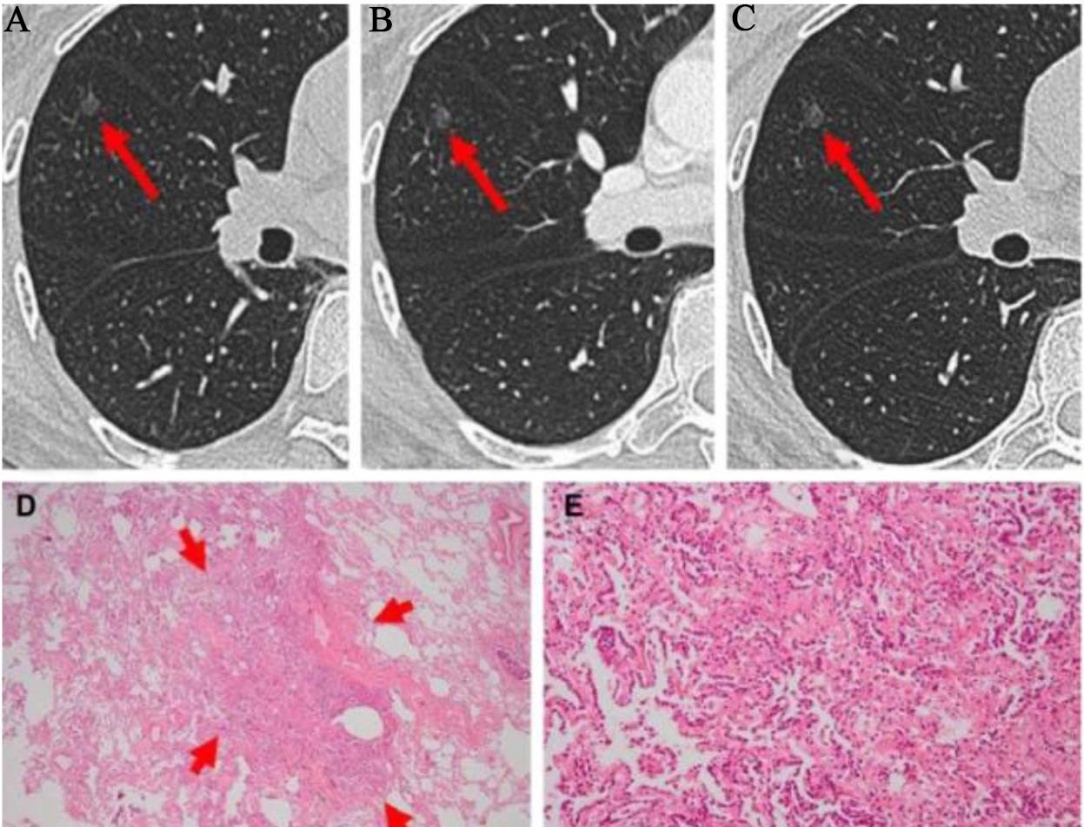

肺腺癌的发展是一个持续的过程,目前主要认为其源于不典型腺瘤样增生,不典型腺瘤样增生常较局限,以肺泡II型细胞和/或Clara细胞增生为特点,衬覆于肺泡壁大体上,细胞间存有空隙且不延续,结节直径常 ≤ 5 mm (见图1);之后发展为原位腺癌,肿瘤细胞继续沿肺泡壁生长,肺泡腔无聚集,无间质、血管及邻近胸膜浸润(见图2);若此时不予干预,放任肿瘤继续生长则有可能微浸润腺癌,直径多 < 3 cm,表现为贴壁生长的孤立结节,伴有1处或多处 < 5 mm浸润灶,大多数微浸润腺癌为非黏液性(见图3);微浸润腺癌再往下发展即是浸润性腺癌[27]。大体标本上,浸润性腺癌多表现为界限不清的灰黄色外周型病变,可为单发或多发。部分肿瘤分泌大量黏蛋白,呈胶冻状或蛋白样外观,空洞形成较为少见。约65%的腺癌位于肺周边,常邻近脏层胸膜,可引起胸膜纤维化或皱缩。少数周围型腺癌可播散至胸膜间隙,广泛覆盖脏层与壁层胸膜,形态类似弥漫性间皮瘤极少数腺癌表现为支气管内息肉样肿块[28]。需要注意,贴壁型生长模式并非肺原发性腺癌特有,亦可见于转移性肿瘤(如来自乳腺或甲状腺),这些肿瘤TTF-1也可能呈阳性。利用肺腺癌这些组织生长的特点,人为进行病理分级,为临床提供肿瘤分期,把握治疗时机,并对治疗方案效果做正确的评估具有重要作用。

Figure 1. Atypical tumor-like hyperplasia of the lung

1. 肺不典型瘤样增生

Figure 2. Lung adenocarcinoma in situ

2. 肺原位腺癌

Figure 3. Pulmonary minimally invasive adenocarcinoma and pulmonary adenocarcinoma in situ

3. 肺微浸润腺癌

图1(A)显示右中叶有一个2.8 cm的磨玻璃样结节(橙色箭头所示)。未发现纵隔淋巴结肿大迹象。图1(B)显示可见肺实质一个边界清晰的肺泡腔区域,其内衬有细胞体积增大、核明显增大的区域以及轻度核多形性。图2(A)~(C)显示一种持续存在的云雾状阴影,病理切片如图2(D)所示,镜下可见立方形、相对均匀的肿瘤细胞群体覆盖增厚及保存完好的肺泡壁。图3影像显示右肺上叶发现了一个孤立的磨玻璃样阴影结节。病理切片显示病变主要由鳞状肿瘤生长组成,伴有几个厚度小于5毫米的侵袭性腺泡成分(箭头所示)。注:以上图片来源于参考文献[38]-[40]